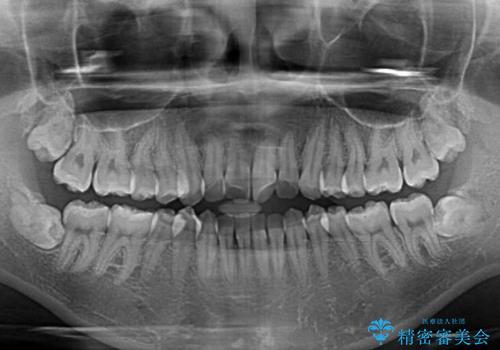

- 海外留学を前に上下のデコボコと奥歯の咬み合わせを改善したいとのことで来院された患者様です。

期間が限られていたため、ワイヤー装置による矯正治療を行うこととしました。

治療開始から4ヶ月ほどで概ね歯列が整い、その後の3ヶ月で細かい部分を仕上げていきました。